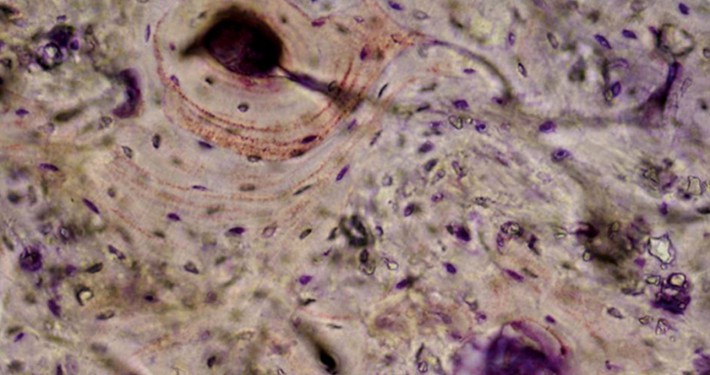

The formulation of CERASORB® Paste is based on developments in modern bone biology. Very fine CERASORB® M granulate is suspended in a hyaluronic acid matrix. This special, patented combination optimally supports the physiological healing process.

After application, CERASORB® Paste takes up growth factors by diffusion from the surrounding bone tissue. The hyaluronic gel provides a matrix for the infiltrating cells with on which the fine CERASORB® M granules can be included. The hyaluronic acid gel does not harden. Its properties make it possible to remain a permanently ductile, volume–stable hydrogel in the defect, where it supports the body’s own healing process.